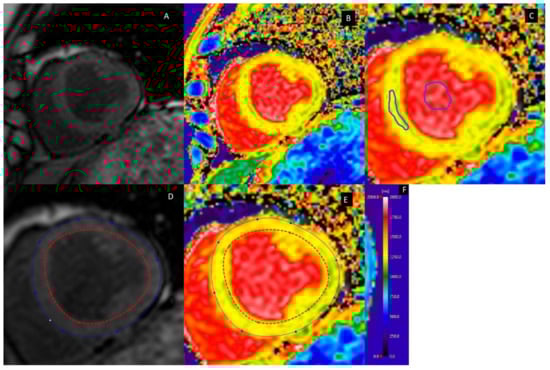

2.2. Myocardial Fibrosis